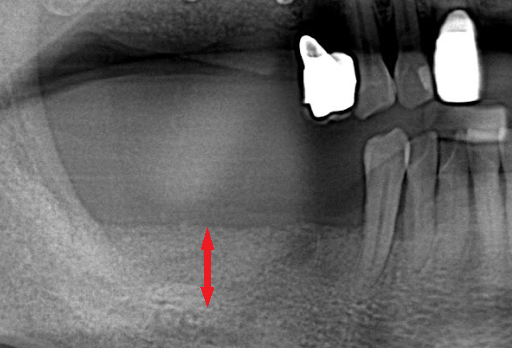

嚴重缺牙的後果? 不管是蛀牙導致的缺牙、退化所致的缺牙、意外造成的缺牙,嚴重缺牙最先會面臨到的問題是「營養流失」,長時間無法正常咀嚼、進食,吸收不佳的情況下,會導致營養不良。 此外,嚴重缺牙會讓口腔上下顎,無法對襯咬合,導致嘴巴無法正常閉合,除了影響美觀,長久下來,也會影響顳顎關節(temporomandibular joint)、咀嚼呼吸系統。 長時間缺後牙的後果? 「缺後牙沒有關係阿,反正看不到,用前面的牙齒咬就好」。這真的是大錯特錯的觀念,長時間缺後牙、錯失黃金治療期,後果,並非想像中的那麼簡單! 「上方後牙區缺牙」,會造成下顎後牙的牙齒往上移,導致錯位咬合,牙脊高度流失、上顎鼻竇腔膨大下墜。之後如果要植牙時,必須伴隨補骨、牙脊增高術或者上顎竇增高術。 「下方後牙區缺牙」,會造成上顎後牙的牙齒往下墜,導致錯位咬合,錯失黃金治療期,會讓牙脊高度、寬度流失,導致缺牙區沒有空間做假牙。 - 假牙的種類 2026.01.19

數位植牙的好處? 不管採取何種植牙治療方式,「4D微創導航系統」牙科技術能夠輔助醫師,在治療時,除了能透過醫師臨床的經驗與技術外,更能精準的控制與判斷病患的所有狀況,降低療程時可能發生的風險,以及減緩術後的不適感。 醫師會在病人的缺牙上,裝上一顆如同「監視器」的機器,搭配「4D動態導航系統」牙科技術,讓醫師在植牙的時候,能夠即時、精準的監測病人口腔骨頭內的狀況。 植牙有黃金治療時間嗎? 植牙的黃金治療期是「越來越快好!」為什麼是「越快越好呢?」最主要是因為牙齒與牙槽骨是相互依存的關係,當缺牙的第一年,骨頭會吸收得特別快,接下來每年以等比的速度吸收。 當口腔內的牙齒,有任何問題或是已經出現缺牙的情況,應該盡快尋求牙醫師的協助!進行治療與骨頭重建的需求評估,已避免增加重建的困難度,甚至無法治療。 到底適合「植牙」,還是要做利用兩邊牙齒做「牙橋」,最終還是需要經過醫師的專業判斷。 如何在茫茫醫海中,尋找適合的植牙醫師? 「一般牙科、贋復補綴科、口腔顎面外科、牙周專科」現代人很喜歡上網做功課,但想要找植牙醫師時,卻不知道從何尋找到適合的植牙醫師。 其實,能夠提供患者專業植牙技術的醫師,通常會受過「贋復補綴科、口腔顎面外科、牙周病科」這3大科的專業訓練。 擔心花錢後植牙出現問題又無法處理,如果長期看診的牙醫診所沒有相關的專業醫師,可以請醫師幫忙轉介。 另外,也可以挑選幾位自己喜歡的醫師,進行面診諮詢,找出最適合的醫師。最後,與醫師充分的溝通、配合也是植牙成功與否的重要關鍵。 植牙的步驟 植牙的流程大致可以分為幾個階段:資料蒐集、資料分析與重建理想牙位、植牙手術與植牙臨時假牙製作,以及最後最重要的植牙假牙製作。 植牙諮詢的第一步「資料蒐集」 資料蒐集、分析: 先利用口腔掃描機、臉部掃描儀、X光片、斷層掃描等,蒐集病患口腔整體環境、牙齦、骨頭的臨床資訊,以及紀錄顳顎關節與咬合的情況。 植牙手術 植牙手術:在經過專業的醫療團隊,進行術前評估後,以及擬定個人化的治療方針後,就會進入植牙手術的步驟,手術的步驟,會先進行牙齦翻瓣、鑽孔、植入人工牙根、縫合、拆線等。 不少人聽到上述步驟,或許已經頭皮發麻,專業的醫療團隊在治療的過程中,會搭配「舒眠麻醉」治療,能夠降低病患在過程中的不適感與恐聚感。 而通常人工牙根的癒合期大約需要6-12週的癒合,待癒合後才會進入「植牙臨時假牙製作」的製作。 植牙永久有效? 植牙有保固期 ? 「植牙成功後,就一勞永逸了嗎?就不用與醫師相見了嗎?」植牙它是鈦金屬釘子,植入骨頭癒合後,它不會蛀牙。但是,植牙周圍的牙肉跟骨頭,如果不妥善保養的話,還是會導致牙周病的發生,就是所謂的植體周圍炎。 植牙上方接出的牙冠,就好比買一台車,牙冠用久了,就如同車子用久了,零件、螺絲依舊會出現損毀的狀況,所以定期的回診保養追蹤是相當重要的。 通常植牙牙套完成後,至少半年回診一次,讓牙醫師檢查確認植牙附近牙齒沒有累積牙箘斑牙結石、植體周圍牙肉沒有發炎化膿,中間固定的螺絲沒有鬆動、牙套沒有破損、咬合狀況穩定等。 此外,患者必須維持良好的口腔清潔,可以參照之前我介紹的牙齒清潔方式,來保持好的口腔衛生、少抽菸等,如此搭配定期的回診檢查,可延長植體壽命。 植體的構造 植牙的治療過程很漫長,很多病患最常問的是「嘴巴內裝上的到底是什麼東西?」 今天的「植牙芯教室」就要帶你來認識「植牙整體的構造」(Dental implant) 口腔內的植牙由上→下依序是:牙冠、支台體、植體。 牙冠:又稱假牙冠、牙套,它是提供如同真牙的咀嚼功能,並且恢復美觀,永久性的牙冠最常見的材質為:全瓷、金屬合金、瓷熔合金屬。 支台齒:連接牙冠與植體的延伸部分,在中間點扮演重要角色,因為它必須要支撐牙冠的咬力,同時又要提供牙肉健康的生長環境,所以專科醫師在安裝時,必須依造病患口腔的狀況「客製化」的設計,ˊ尋找最適合的形狀、大小與角度。 植體:置入於缺牙的牙槽骨中,功能是取代原有的「牙根」,負責穩固牙齒的地基,目前最常見的植體材質為純鈦、鈦合金。 植牙x牙冠材質 對於越來越講求美觀的現代人來說,花錢植牙,當然希望它能美觀性與功能性兼具。 今天的「植牙芯教室」就要帶你來認識「牙冠材質」 目前,市面上永久性的牙冠最常見的材質為全瓷、金屬合金、瓷融合金屬 。 1.全瓷牙冠:材料有氧化鋯、強化玻璃瓷,不需要使用金屬,材質與人體的生物相容性高,同時具備高硬度的特性、高耐磨、耐高溫。在外觀上,呈色自然如同真牙,美觀性極佳。 2.瓷融合金屬牙冠:由於合金的成分複雜,若是高貴金屬的成分(黃金、白金)不夠高時,在口腔高溫潮溼的環境下,金屬容易腐蝕,導致表面粗糙,使牙菌斑難以徹底清潔,就容易造成牙齦發炎,並且染色,長期在美觀上、實用性都難以符合,對於外觀講求自然的病患。 3.金屬合金牙冠:由於整體採用金屬製作,所以不容易破裂、折斷,但是外觀呈現金屬色,所以當張開口時,便能夠一眼看出假牙的位置,如果使用金屬和金的牙冠,建議使用高貴金屬成分較高的材質。 植牙前的注意事項 想要提高植牙治療成功率,醫師與病患互相配合很重要,從術前的資料蒐集、評估與診斷,依據病人的情況,給予專屬的治療方針,從術中的治療過程,到術後的維護都非常重要,先來談談植牙前要注意那些事情。 1.保持口腔衛生:口腔清潔是植牙成功的最大關鍵 2.降低煙癮:抽菸會影響植牙的成功率,應該要盡量避免,如果能夠戒菸成功,更能提高植牙的成功率。 3.持續服用慢性病藥物:如果有在服用慢性病(高血壓、糖尿病等),在術前的諮詢,務必完整提供用藥歷史給醫師。 植牙後的潔牙步驟-工具篇 「植牙疏於潔牙與保健,百萬台幣立刻船過水無痕。」這是血淋淋的案例,真的不要以為,植牙完成後就一勞永逸。 術後的口腔清潔與維護非常重要!非常重要!非常重要!因為植牙的「使用壽命」,有非常大的關聯性。 植牙維護有三寶:牙刷、牙間刷、牙線 牙刷:可以選擇自己習慣的刷頭,或者選擇刷頭短小、刷毛軟硬適中的牙刷 牙間刷:當牙齦萎縮、牙縫變大時,應該選擇適合牙縫大小的牙間刷,用來清潔齒間的縫隙、牙套底層的牙菌斑與食物殘渣。 牙線:使用超級牙線,來清潔牙橋下的支柱牙部分。 漱口水、沖牙機等,這些只是輔助工具,千萬不能把它當作正規的潔牙器材。 植牙後的潔牙步驟-清潔篇 植牙的清潔方式。 首先:使用牙刷在假牙與牙肉的交界,採用刷牙法,來回輕刷至少10次。 接著:使用牙間刷,輕貼牙齒的表面,進行前後清洗,按照同一個方式,從舌側進入,輕貼牙齒表面,再做一次清潔,每次動作至少5次。 最後:使用大約45CM的牙線,可以使用穿引器的輔助,深入牙橋底下做清潔,每次動作至少5次。 植牙後的潔牙步驟-電動牙刷VS.一般牙刷 「做完牙套後可以用電動牙刷刷牙嗎?潔牙工具怎麼選?」上一篇,談了植牙的清潔方式,究竟植牙到底該不該用電動牙刷?答案是「可以」。 科學研究指出,使用電動牙刷,能更深入清潔到牙縫與牙齒倒凹處,尤其對於手部協調性沒那麼高的人,以及牙齒排列凌亂者,在清潔上能夠達到更好的效果。 刷頭的選擇:一樣要以刷頭小、刷毛軟硬度適中的刷頭,建議每1-3個月,或者外觀出現彎曲變形,刷頭就必須更換。千萬不要因為刷頭,比一般牙刷貴捨不得更換,反而會讓潔牙效果打折扣。 潔牙方式:電動牙刷與一般牙刷的潔牙方式的差異在於,電動牙刷只需要將刷頭輕放在單顆牙齒上,讓刷頭在牙齒與牙肉的交界處轉動,手不需要來回移動刷頭。但是千萬不要重壓,施壓過多的力道在牙齒上,反而對於牙齦是種傷害。 另外,不管使用電動牙刷或一般牙刷,都一定要使用牙線、牙間刷,來清潔牙齒與牙齒間的鄰接面,確保牙菌斑被清除。 潔牙時間:三餐飯後,30分鐘內如果能夠潔牙是最好的,如果無法達到,睡前徹底的潔牙是最重要!另外,潔牙時一定要有耐性,不要為了節省時間,隨便刷2.3下就結束。 如何選擇:預算、操作與攜帶方便度為首要考量,而且選擇具有「經濟部標準檢驗局」檢驗合格的產品,設計不良的電動牙刷,可能會造成口腔受傷。 植牙後的術後照護 植牙的最終成功與否,術後照顧真的非常重要!務必遵從醫囑,以下是照護的重點。 1.冰敷:術後1周,依舊會有些許的腫脹與輕微的瘀青,在48小時內,建議患者可以冰敷,在臉頰外側冰敷15-20分鐘,休息10分鐘,重覆動作到48小時。 2.不要泡溫泉、熱水澡,以及從事游泳與劇烈的運動。 3.飲食方面:初期還是會建議以流質、軟度高的食物為主,過燙、過冰的流質食物則不宜,應該避免食用過燙、辛辣、含有酒精成分刺激性的食物。 4.降低菸癮:為了讓植牙的傷口能順利恢復,醫學上皆有文獻記載,術後1周必須降低菸癮。 5.定期回診:植牙完成還是必須定期回診,讓醫師確認傷口、口腔健康的情形。 根據手術療程的不同,每一項術後的照護方式也有所差異,未來會跟大家分享與討論。 植牙後就能一勞永逸,不會有牙周病? 大多數的病患都知道,植牙前要先把牙周病及其他口內問題處理好,以降低口內細菌數量,才能夠進行植牙,但是很多病患以為,植牙成功,同時也能跟牙周病永久說再見,這觀念完全不正確。 簡單說「牙周病」是牙齒的周圍骨頭受到細菌的破壞,所造成的結果。因此,在植牙後,如果植體周遭的牙肉與骨頭,沒有得到妥善的清潔與照顧,還是會造成口腔內細菌的滋生,一樣會導致牙周病的發生。 植牙後,是不是也跟敏感性牙齒Say Bye Bye 一般所說的「敏感性牙齒」真正的學名是「牙本質知覺敏感症(Dentin Hypersensitivity)」會造成敏感性牙齒,主要原因是在於牙齒外層的琺瑯質被磨耗後,失去保護的功能; 或是牙齦萎縮牙根裸露時,都會造成牙本質內的神經小管暴露,當受到冷熱、吹氣、和壓力等刺激下,所產生的神經疼痛不適感。 植牙後,重建的人工牙冠內沒有神經,所以不會有敏感性牙齒的發生。然而,其他的自然牙齒,不會因為植牙而受到改變,當琺瑯質被破壞時,依舊會造成牙齒敏感性的問題。 骨質疏鬆的人適合植牙嗎? 「骨質疏鬆」有越來越年輕化的趨勢,除了因為年齡的增長之外,身體未獲得適當的保養也是元兇之一。如果是輕微的骨質疏鬆,只要適當的補充鈣質,想要植牙依舊沒有問題!整體還是必須交由專業醫師評估。 「骨鬆患者」,尤其是有在服用高劑量或施打抗蝕骨作用的藥物,是會影響植牙的成功率。原因在於,大多數的抗骨質疏鬆藥物,含有雙磷酸鹽,會影響骨骼細胞修補的功能,讓顎骨無法修復。所以如果有服用相關藥物,植牙前一定要告知醫師。 我是高血壓患者,能夠植牙嗎? 在高血壓控制好的前提下,是可以進行植牙手術的!正常的血壓是指收縮壓120/舒張壓80mmHg,當血壓偏高時,會增加手術中的出血狀況,提升手術的複雜度,甚至會提高手術後的感染率。 很多高血壓患者會服用「抗凝血藥物」。「抗凝血藥物」可能會在手術時,出現傷口流血不止的問題,所以醫師在進行植牙評估時,一定要讓醫師了解自身的慢性病史與用藥,並且盡可能尋找能提供詳細治療計畫,以及擅長微創植牙手術的醫師,降低植牙的風險。 我是糖尿病患者,能夠植牙嗎? 糖尿病患者與高血壓患者,都是在控制良好的前提下,能夠完成植牙手術。由於糖尿病控制不良的患者,細胞修復的能力與免疫系統,跟正常人比起來比較低,相對的牙周組織再生能力、傷口癒合情況也比較差。 所以想要植牙,必須同時與新陳代謝科醫師與植牙醫師相互合作,穩定血糖。除此之外,糖尿病患者也應該養成良好的口腔保健習慣,在經過醫師的專業評估,提供完善的治療計畫。 糖尿病與牙周病的關係? 「牙周病已經被列為糖尿病的併發症之一」前面談到「只要控制好血糖」依舊能夠植牙。我們也提到植牙前,一定要把牙周病控制住。今天我們就來談談「牙周病與糖尿病控制不良的關係」。 事實上,糖尿控制不良的病患發生牙周病的機率是正常人的3倍。最主要的原因,口腔細菌量會比正常人多,由於免疫系統比較差,更容易受到感染,所以傷口的復原能力也較低。 一旦糖尿病控制不良者得到牙周病時,病程也會跟著加速,骨頭被破壞與受損的速度也會加快。並且,因為身體長期發炎,將會導致血糖更不易控制。 癌症患者適合植牙嗎? 「癌症已經連續多年佔據國人10死因的首位」而癌症到底能不能進行植牙手術呢?首先,醫師會先了解病人的癌症種類與期數,以及過去的病史、治療史、用藥史,經由病人提供的資料,來做精準的判斷。 癌症的放射治療、免疫抑制等是會影響到傷口的癒合,治療上會使用到,抗骨吸收藥物 (antiresorptive agents)與抗血管生成藥物(antiangiogenic agent)等,都很有可能增加顎骨壞死的風險。另外,頭頸部經過放射線照射後,也會造成骨細胞的活性降低。 而且病人在接受化療、標靶藥物時,也會因為治療後,免疫力降低,細胞修復能力變弱,如果在治療期間,或是在治療後,想要做植牙,都應該先找醫師進行評估身體各項數值,以提高植牙成功率。 懷孕期間能夠植牙嗎? 雖然植牙是一個小手術,但是通常醫師都不會建議準媽咪們,在這時候進行植牙手術,首先,因為植牙是必須照X光檢查,在懷孕期間,應盡量避免暴露在輻射線下。 同時植牙必須經過麻醉的步驟,雖然麻藥會經由尿液排除體外,但大多數麻藥都含有「血管收縮劑」的成分,在治療過程中引發的加倍焦慮,可能會造成者子宮提前收縮的風險。所以會建議想植牙的準媽咪,產後再進行植牙手術。 產後、哺乳期植牙注意事項 「醫師,我正在哺乳期能植牙嗎?」在懷孕期間,就算已經完成第一階段的植牙手術,醫師為了保護母體與胎兒,會直接將療程暫停至產後,但是女性「產後要多久才能植牙?」、「哺乳期能植牙嗎?」成為許多媽媽最常問的問題。 事實上,女性產後的身體狀況恢復到一定的程度,就能夠進行植牙。而為了擔心麻醉藥或是抗生素、止痛藥分泌到母乳,加上每種藥物的半衰期不同,通常會建議,服用完最後一次藥物,在相隔24小時後,才進行哺乳。 服用健康食品是否會影響植牙 「維他命C、B群、魚油、銀杏、補鈣產品...」各式各樣的保健食品有吃有安心,很多病患到了診間,最常問我的問題之一「醫師,我有在服用各類的保健食品,會影響植牙嗎?」 事實上,需要看服用保健食品萃取的成分而定,不是所有的保養品食品,都會影響植牙的。如果營養品中含有「抗凝血作用」成分的保健食品,例如:銀杏、紅花。會建議在術前1周暫停服用。 雖然,適當的服用保健食品,確實有益於健康,但是在進行植牙評估時,還是務必告知,讓醫師做更正確的評估。 植牙要局部麻醉還是全身麻醉? 「植牙到底要全身麻醉,還是局部麻醉?麻醉的方式有哪些?差異性、有沒有後遺症?」許多病患都會有相同的疑問,從今天開始,一連串的文章來解惑。 其實,植牙手術跟一般口腔治療的方式一樣,能夠在病患清醒情況下進行治療,醫師通常會使用局部麻醉藥內含少比例血管收縮劑(Epinephrine),針對病人的手術內容,與治療所需的時間,給予準確的麻醉劑量。 由於大部分的局部麻醉藥,含有血管收縮劑,之前文章有提到高血壓的患者,必須在做治療諮詢時,提供用藥史與血壓控制情形,並且在手術當天,都應該接受血壓的測量,已確定用藥的安全性。 植牙的成功率?植牙失敗怎麼解?植牙的後遺症? 「植牙能100%成功嗎?植牙後是不是就再也不用回診?當植牙開始出現問題時,怎麼辦?植牙失敗後該如何治療?」這些問題是現在病患在選擇植牙時,很重要的考量。 「植牙成功率及植體壽命的長短」其實,最重要的是取決於醫師、病患有沒有合作無間,醫師與病患都應該在治療的過程中,扮演好彼此的角色,才能在植體成功骨整合後,延長使用的壽命。 病人,在諮詢時,要確實的將藥物史、病史提供給醫師。在治療期間,遵照醫囑、落實口腔衛生,並且在術後定期回診。此外,當植體出現任何情況時,必須立刻尋求醫師的協助「及早發現、及早治療」。 醫師,在技術、經驗上必須給予病患精準個人化的治療方針,並且選用大品牌的植體、生物醫材,提高治療成功率。同時,隨時吸收醫療新知,並將它運用,讓病患得到最好的治療。 上述都是植牙成功不可或缺的關鍵之一。 植牙後出狀況x牙冠瓷破裂 「植牙後出狀況怎麼辦?」 就如同之前所說,植牙就像是一部車子,用久了零件會出現受損的情況,要聊「出狀況怎麼辦?」就要回歸問題的根源來對症下藥,接下來,我將針對「植牙後常見的幾大狀況」來做詳細的說明: 牙冠瓷破裂:可將假牙取下,送修補瓷以回復美觀及咬合功能。因為牙科材料學的進步,新式二氧化鋯牙冠 (Zirconia),幾乎不會有破裂的狀況,這也是目前牙冠材質中,在品質與美觀上的表現,都擁有較高的穩定性。專業的贋復醫師在修復之前,會先把連接體跟牙冠中間的隙縫清潔乾淨,讓植體免於細菌感染的風險。 植牙後出狀況x植體配件的鬆脫、受損 「植體配件的鬆脫、受損」,之前的植牙芯教室,我們有介紹,牙冠與支台齒內含有各種不同的小零件,當植體用久了,零件開始出現狀況,該如何處理? 要談到該如何處置之前,要先了解,為什麼會發生「植體配件的鬆脫、受損」的狀況,大致可以把原因歸類為:零件壽命、植體長期咬合受力。 病患完成植牙後,在每半年的定期回診,牙醫師都會針對這些細部零件做確認,確定是否有鬆脫或晃動的情形出現。 一旦出現螺絲的鬆脫情況,沒有及時治療,螺絲就會斷裂在植體內,而要從植體內,將斷裂的螺絲取出,是件複雜又具高風險的療程,必須由經過專業訓練的植牙贋復科醫師來做處置,在往後的文章,將再做更詳細的說明。 植牙的麻醉方式有哪些? 「舒眠麻醉、全身麻醉、笑氣麻醉」這是目前大家在搜尋資料時,比較容尋找到的關鍵字,今天就來簡單介紹,這些麻醉的專有名詞。 舒眠麻醉:目前贋復科醫師最常使用的麻醉方式,屬於淺層麻醉,能夠讓病患在放鬆的情況下進行治療,也能夠降低局部麻醉的用藥量,關於「舒眠麻醉」接下來會一系列的介紹。 全身麻醉:屬於深度麻醉,麻醉藥的劑量會讓病患意識消失,而且無法自主呼吸,術後的恢復期較長,必須要在開刀房內進行。 笑氣麻醉:主要是用來鎮靜,而非麻醉,有些病患在做口內局部麻醉時,依舊會感受到看牙的緊張感,因此,有些醫院或診所,會備有笑氣設備,幫助病患在局部麻醉時,能夠鎮定。 植牙的評估要件懶人包 Q:缺牙會影響到那些層面? A:身體、心理都會受到影響,長期缺牙會讓導致「咬合障礙」 Q:到底要植牙,還是要做假牙? A:需要經過醫師的專業評估與判斷,「假牙」與「植牙」各有優、缺點。 Q:幾歲適合植牙? A:只要經過牙醫師臨床的評估,不管是25歲較年輕的缺牙病患,或者80歲的族群都能。 Q:如何在茫茫醫海中,尋找適合的植牙醫師? A:專業植牙技術的醫師通常會受過「贋復補綴科、口腔顎面外科、牙周病科」3大科的專業訓練。 Q:怕痛的人,如何進行植牙手術? A:現在也出現了「舒眠治療」,讓患者在治療上,大幅減低焦慮感。 Q:我是高血壓患者能植牙嗎? A:在高血壓控制好的前提下,是可以進行植牙手術的! Q:骨質疏鬆的人適合植牙嗎? A:如果是輕微的骨質疏鬆,只要適當的補充鈣質,想要植牙依舊沒有問題。 Q:癌症患者適合植牙嗎? A:在癌症治療期間或是在治療後,想要做植牙,都應該先找醫師進行評估身體各項數值,以提高植牙成功率。 Q:懷孕期間能夠植牙嗎? A:植牙必須經過麻醉的步驟,所以想植牙的準媽咪,產後再進行植牙手術。 Q:服用健康食品是否會影響植牙? A:需要看服用保健食品萃取的成分而定,不是所有的保養品食品,都會影響植牙的 舒眠治療懶人包 Q:舒眠治療有健保給付嗎? A:舒眠自療跟植牙如同屬於自費項目,並無健保給付。 Q:舒眠治療前需要做哪一些準備? A:由於治療藥物的濃度,與個人身體狀況與病史有關,所以患者必須確實告訴醫師用藥的習慣以及病史,必要時,在舒眠治療前,醫師會要求病患,先做身體健康檢查。 Q:平常有習慣吃保健食品需要暫停嗎? A:大部分的保健食品都不需要停藥。 Q:舒眠治療需要禁食嗎? A:需要的,必須至少禁食6-8小時,如果是在上午進行,前晚12時之後就不可飲食,如果是下午,則是早餐過後,就不能進食。 Q:舒眠治療前的禁食,若有需要服用藥物該怎麼辦? A:禁食期間,服用少量的水吃藥是被允許的。 Q:有服用抗凝血藥物怎麼辦? A:通常不需要停藥,除非是經過專業醫師指示,才需要停藥。 Q:舒眠治療當天可以駕駛嗎? A:舒眠完成後,可能會有頭暈的狀況出現,建議在親朋好友陪同下,搭乘交通工具前往診所。 Q:舒眠治療後的注意事項? A:在完成治療後,患者應休息20-30分鐘,確保沒有暈眩、嗜睡的情況發生,才能離開診所。 植體品牌 ║史得勞曼(Straumann)║ 瑞士的植牙品牌,經過許多臨床醫學研究證實,是植體品牌中邊緣骨流失最少的系統之一,其特殊植體連接體的設計,使牙冠與植體緊密結合,增加假牙的穩定度,降低鬆脫、晃動的機率。 →https://reurl.cc/8lDo1X ║諾保科(Nobel biocare)║ 瑞典的植牙品牌,在2008年推出的NobelActive系統,植體特殊的螺紋設計及表面處理,適用於骨質條件狀況比較複雜的患者。 →https://reurl.cc/xDN9zL ║亞仕特(Astra Tech Implant)║ 瑞典的植牙品牌,在植體與連結面的設計上,採用特殊的圓錐六角形內接式的設計,穩定的接口,能降低牙冠與支台齒,鬆脫的情形。 →https://reurl.cc/jd91bn ║百好(BIOHORIZONS)║ 來自美國的植體品牌,BioHorizons採用硬度、生物性較高的鈦合金材質,同時擁有特殊的Laser-lok專利技術,不僅能降低植體牙周病的發生機率,又達到兼顧美觀的功能。 →https://reurl.cc/YlYvZn ║貝格莎曼杜(BEGO Semados)║ 德國在地生根、製造生產超過125年的歷史悠久,植體表面特殊的TiPure技術,能夠幫助植體與齒槽骨結合,達到最大的整合功能,同時,也能幫助植體壽命的延長。 →https://reurl.cc/oD81ov” - 植牙後的保養 2026.01.19